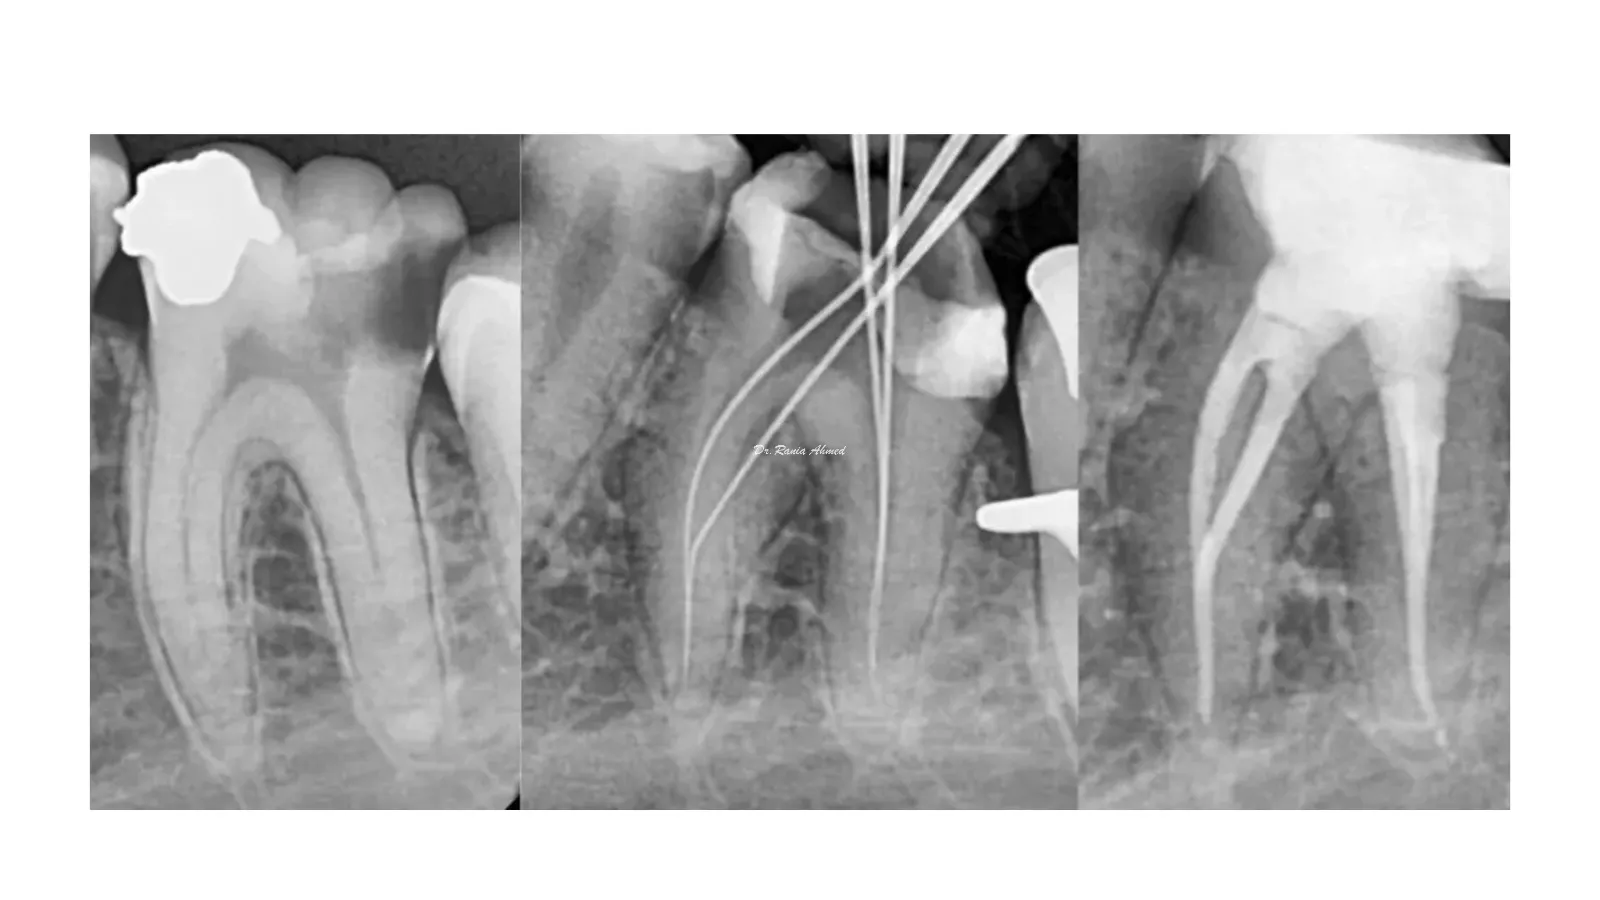

Endodontic Treatment